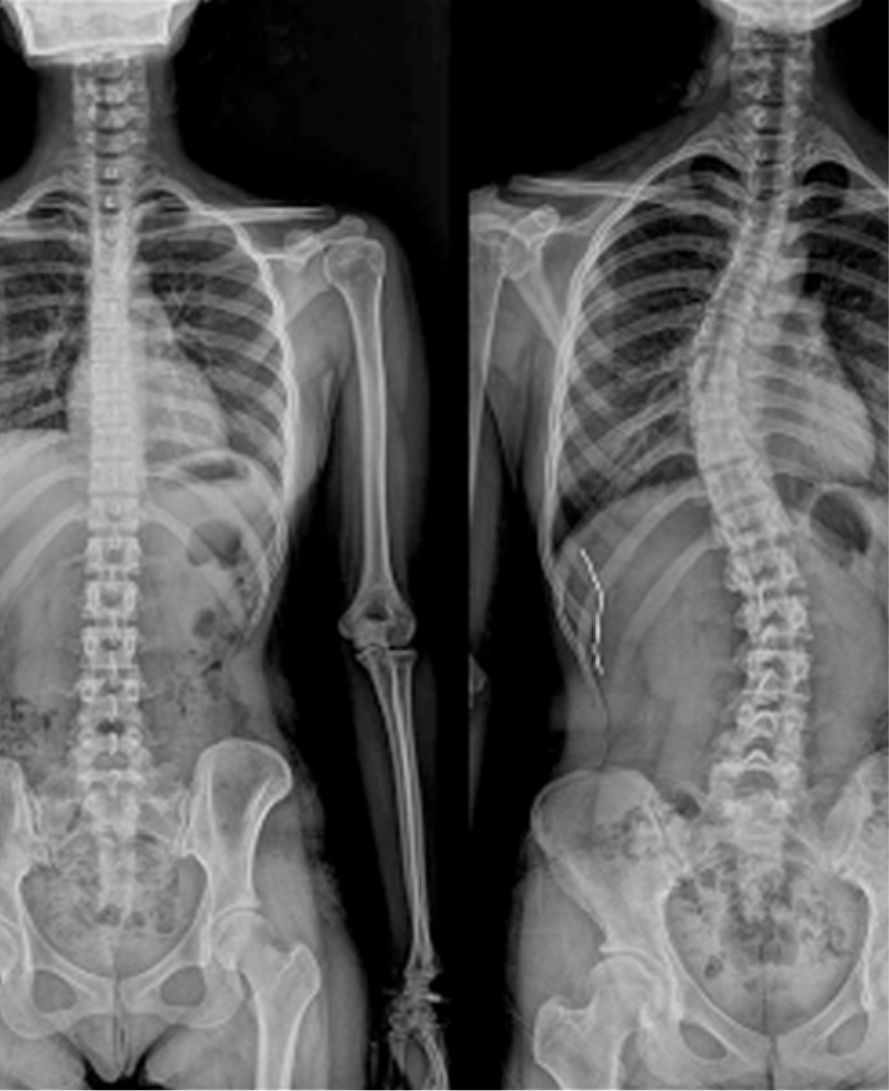

척추측만증

척추가 정면에서 보았을 때 좌우로 휘어진 상태를 말하며,

흔히 S자형 또는 C자형 곡선으로 나타납니다.

성장기 청소년에게 많이 발생하지만,

성인에서도 퇴행성 원인으로 나타날 수 있습니다.

어깨 높이가 다르거나 몸이 한쪽으로 기울어져 보임

골반 비대칭, 갈비뼈 돌출

허리나 등, 목의 만성적인 통증

청소년의 경우 외관 변화 외에 자각 증상이 없는 경우도 많음

X-ray 검사, MRI, C-arm(실시간 영상장비) 유도 하 주사

관찰 및 추적 검사, 운동치료/도수치료, 보조기 착용

수술적 치료 : 40도 이상 중증이거나 통증 및 기능장애 등